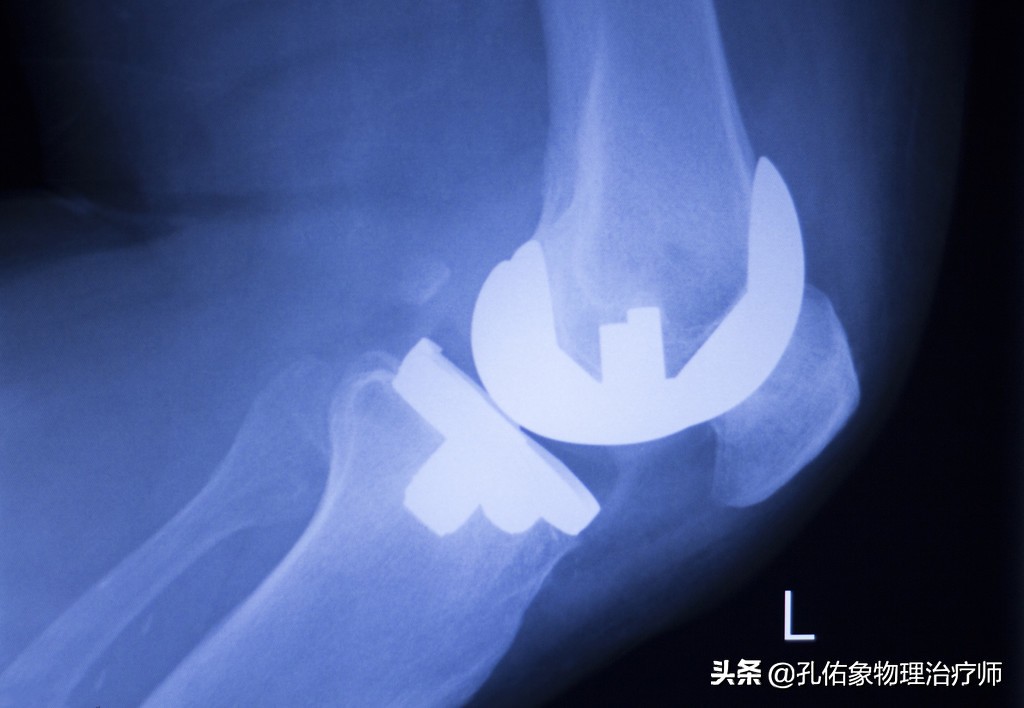

3.若是都到了X片下的关节边缘有骨赘物,关节间隙的变窄,关节变形的阶段。

全层软骨软化的结局

这个阶段就是很多老年人所处的状态,不但上下楼严重困难,就走平路都很痛苦,关节的活动范围已经很小,完全影响到整个人的生活。因为此时的软骨已经全层磨损,直接是软骨下面的骨质在承受负荷,其受到应力刺激时,就会激发骨质上的神经末梢引发疼痛。

还有就是最后一种手术方法,做膝关节置换,就是把膝关节的结构截掉,换上假体膝关节,如下图:

膝置换术

置换术后,拍出来的X片是这样的。

置换后的X片

这个手术呢,相对还是比较成熟的;如果你真是处于这个阶段的问题,影响到你生活质量的话,直接选择这个手术吧,目前没有比这更好的解决方法。当然千万不可忽视术后的康复哈,手术后的康复决定你手术的成败,若是没有功能的膝关节,即使手术做得再完美,也是惘然。